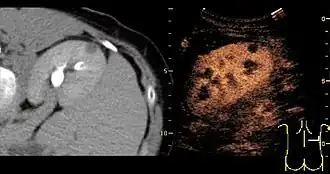

A CT scan is the first choice modality for workup of solid masses in the kidneys. Nevertheless, hemorrhagic cysts can resemble renal cell carcinomas on CT, but they are easily distinguished with Doppler ultrasonography (Doppler US). In renal cell carcinomas, Doppler US often shows vessels with high velocities caused by neovascularization and arteriovenous shunting. Some renal cell carcinomas are hypovascular and not distinguishable with Doppler US. Therefore, renal tumors without a Doppler signal, which are not obvious simple cysts on US and CT, should be further investigated with contrast-enhanced ultrasound, as this is more sensitive than both Doppler US and CT for the detection of hypovascular tumors.[3]

On renal ultrasonography, a solid renal mass appears in the US exam with internal echoes, without the well-defined, smooth walls seen in cysts, often with Doppler signal, and is frequently malignant or has a high malignant potential. The most common malignant renal parenchymal tumor is renal cell carcinoma (RCC), which accounts for 86% of the malignancies in the kidney. RCCs are typically isoechoic and peripherally located in the parenchyma, but can be both hypo- and hyper-echoic and are found centrally in medulla or sinus. The lesions can be multifocal and have cystic elements due to necrosis, calcifications and be multifocal (Figure 8 and Figure 9). RCC is associated with von Hippel–Lindau disease, and with tuberous sclerosis, and US has been recommended as a tool for assessment and follow-up of renal masses in these patients.[3]